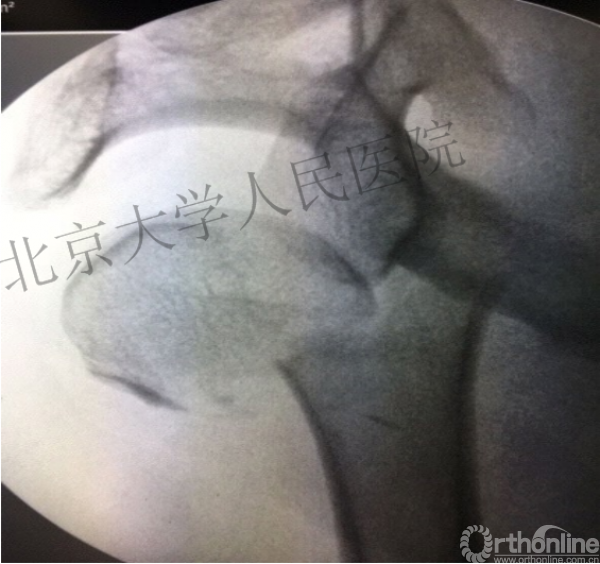

肱骨头复位

克氏针的应用“joystick”

简单骨折的闭合复位技术:以克氏针作为“joystick”

髓内钉的应用复位是关键